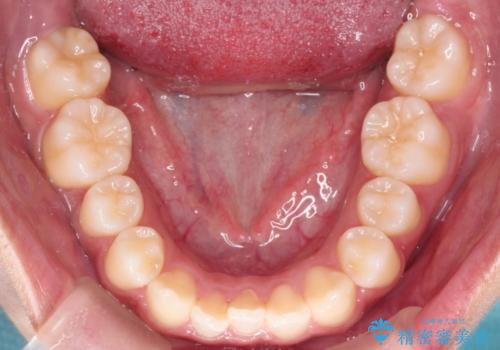

下の前歯が一本足りない患者様でしたので、シミュレーションを作り、事前に患者様と治療ゴールのイメージをしっかり共有したうえでインビザラインを用いて治療を行っています。

下顎の前歯が一本ない場合は上下の正中は合いません。